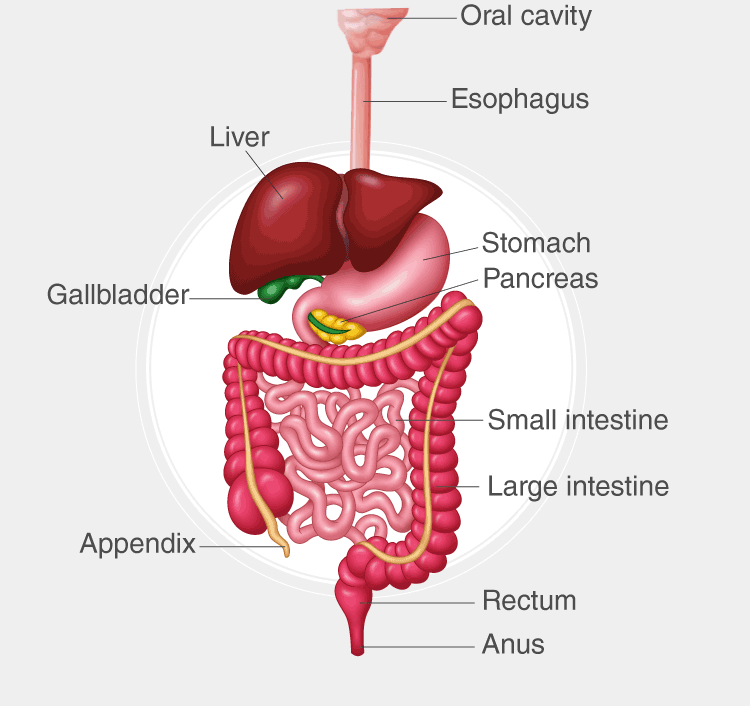

digestive/gastrointestinal cavity

abdominal cavity

mucous membrane

soft tissue that lines the body's canals and organs that are open to the outside

location: digestive, respiratory, and reproductive systems